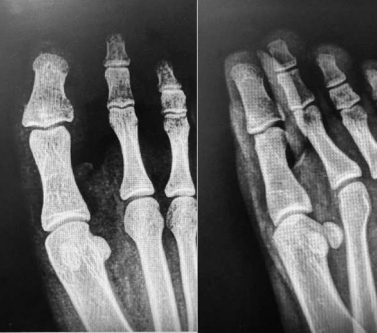

Figure 1: A radiographic work-up included an X-ray of the big toe, which was found to be normal despite the presence of a non-specific condensation at the base of distal phalanx.

Figure 1